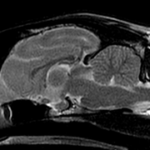

• [MR画像 矢状断像 T2強調画像]

画像で見る病気(飼い主様向け)

#18 頚部脊椎脊髄症(ウォブラー症候群)(飼い主様用)

<症例情報> バーニーズマウンテンドッグ5歳 去勢済みの男の子 主訴:最近首が痛そうで下を…